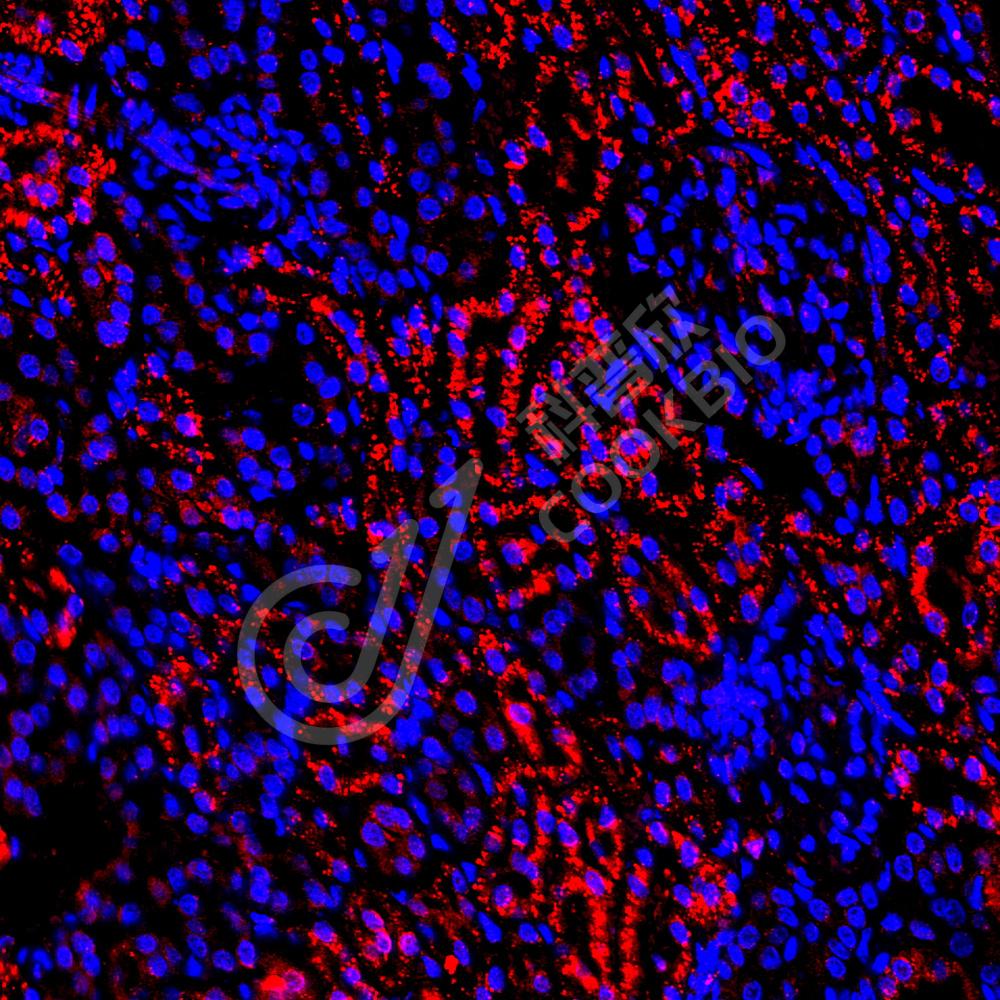

IF检测USP33蛋白(货号 K1337821)(红色).

样品: 人卵巢癌, 4%多聚甲醛 (货号KSG1101) 固定12-24小时.

抗原修复: Tris-EDTA抗原修复液(pH 9.0) (KSG1203), 98℃, 20分钟.

封闭: 3% BSA(货号KSGC305010)的PBS溶液, 室温孵育30分钟.

—抗: 1: 1300稀释, 4℃ 孵育过夜.

二抗: Cy3标记山羊抗兔IgG (H+L) (货号KB63909), 1: 300稀释, 室温孵育1小时.